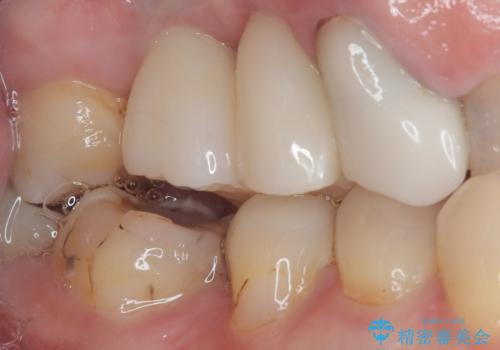

- 欠損や破折により失われた奥歯に、インプラント治療を希望して来院された患者様です。

欠損部はすぐにインプラント埋入が可能で、手前の歯根が残存している部位も、できれば抜歯をして奥と一緒に埋入をしたいところでしたが、破折による炎症が大きいため、2回に分けてインプラント埋入を行うこととしました。